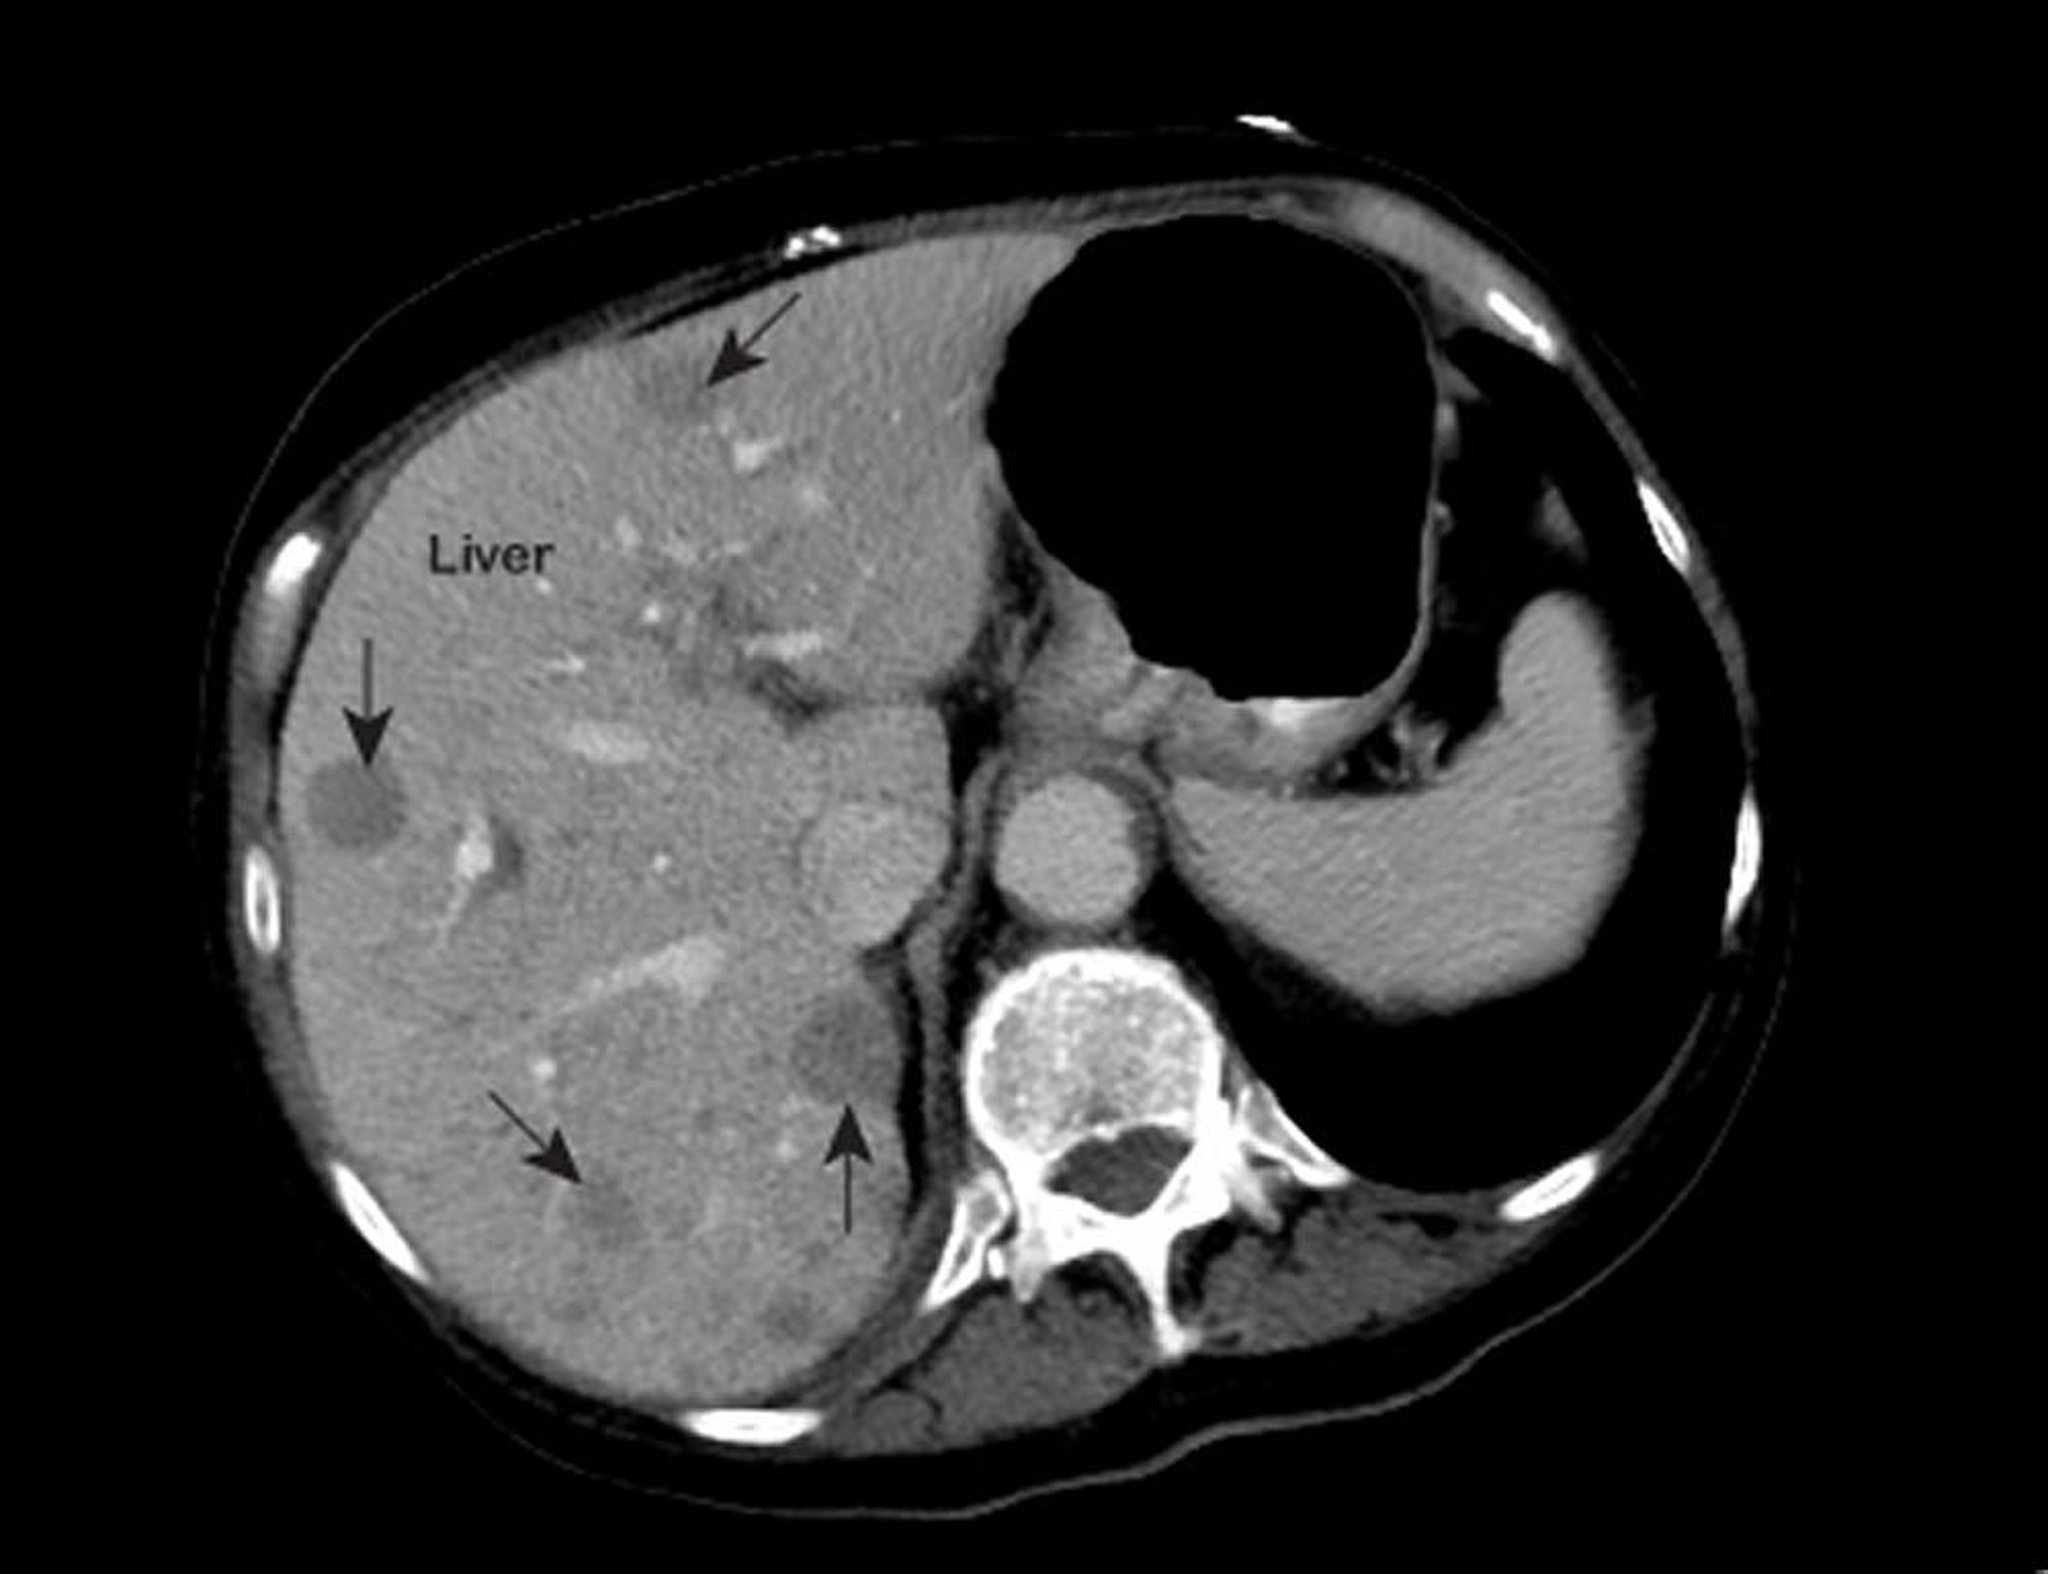

Cáncer metastásico de hígado

Una imagen torácica anormal obtenida mediante resonancia magnética (RMN) muestra áreas anormales (marcadas con flechas) dentro del hígado. Estos hallazgos son característicos del cáncer de hígado metastásico.

Foto cortesía de Patrick O’Kane, MD.